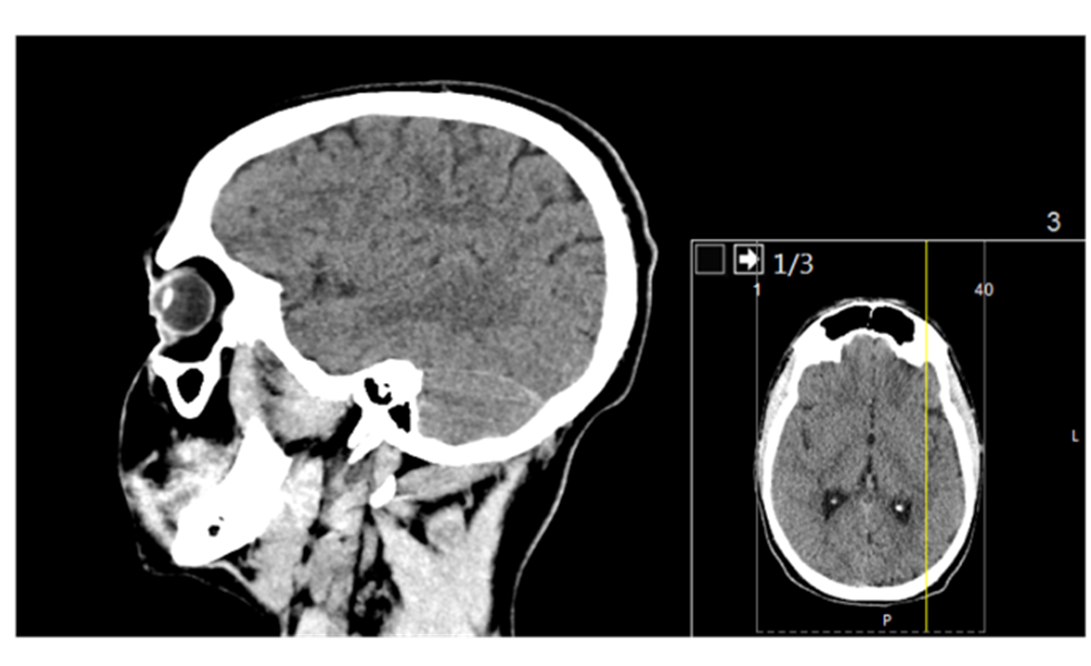

Page 18: Techniques for Visualizing the Brain

Two primary categories of imaging techniques exist for examining the brain:

Structural Techniques:

CT Scan (Computed Tomography): Employs X-ray imaging to produce cross-sectional views of the brain, providing structural data.